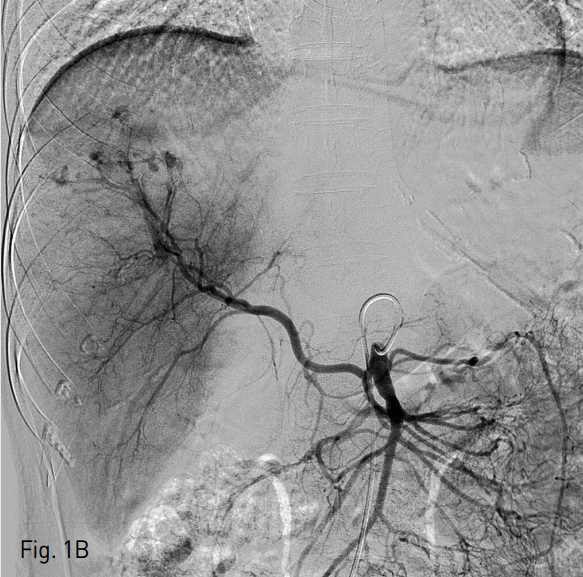

응급실 내원 직후 시행한 복부 CT에서 liver의 4,7,8 segment에 다량의 혈종과 pseudomaneurysm 그리고 multiple active bleeding이 관찰되었다 (Fig.1A). 색전술을 위하여 시행된 혈관조영술에서 replaced right hepatic artery branching off of the SMA를 통한 간 우분절에 다발성의 점상출혈이 있고 (Fig. 1B) 또한 left hepatic artery of celiac trunk를 통한 간 좌분절에도 다발성의 점상출혈이 있어 (Fig. 1C) 색전술을 시행하였다.

B. SMA angiography revealed multifocal active bleding foci in right hepatic segment through the replaced right hepatic artery originated from the SMA.